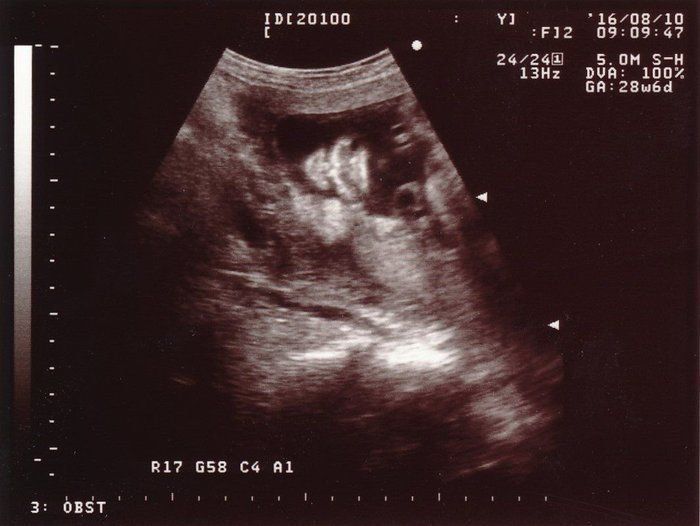

ママにエールさんの妊娠28週目のエコー写真

前回の検診で治ったと言われたはずなのに、またまた“逆子”になっていました。かなりアクロバティックに動き回っている様子。赤ちゃんが元気に動くことで、私のおなかも驚くほどによく変形しました。“逆子”になっていたこともあり、やはり性別は判明せず。先生からは、「次の検診で逆子が治っていなかったら、逆子体操をやってもらいますね」と言われました。